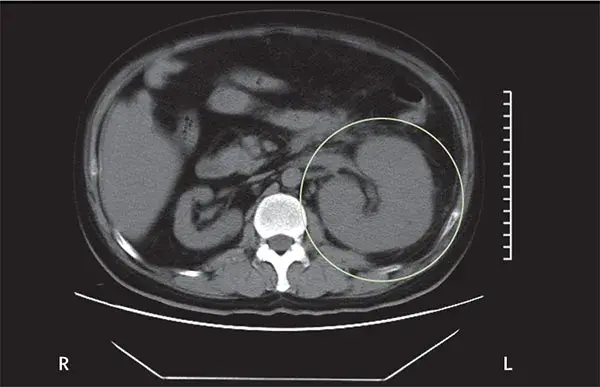

Os cálculos coraliformes são formados em sua maioria por cálculos de estruvita (fosfato amônio de magnésio) e possuem uma forte associação com infecção do trato urinário (ITU) causada por bactérias produtoras de urease. A formação desses cálculos é rápida, semanas a meses, e se não instituído tratamento adequado pode ocorrer invasão completa do sistema coletor